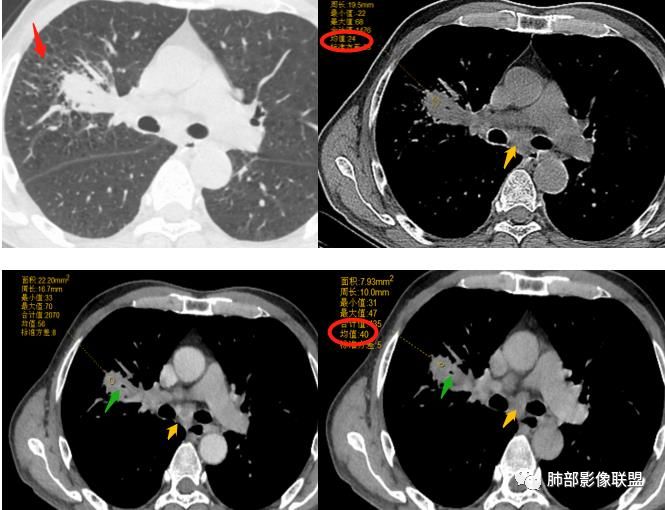

可以看到斜裂一侧往上一侧往下,那么就是说病灶应该是起源中叶,往上,往下侵犯这样

@吴婧南京市第一医院 主体应该还是中叶

往下叶这个地方是突然就鼓出来了,这个地方还是应该叶裂缺限。

如是上叶的,叶间裂的方向应该是往一侧压得

不是上叶

只有这个位置起源得才能做到,将叶间裂上下往不同方向推

斜裂向下推移了,水平裂向上推移了。

@吴婧南京市第一医院 这个从影像表现,坏死情况,以及叶裂推移情况与支气管推移情况来看,还是支持中叶间质来源,外朝内生长,同时向上,向下,向内都有推移作用。

具体的病理类型,把握真的不大,所以我也不勉强,如果非要猜一下的话,整个符合外朝内生长的肿瘤,所以我把肉瘤或肉瘤样癌排前面,低分化腺放后面,鳞癌可能性不大(生长位置不对,支气管堵塞情况不支持,纵隔内淋巴结肿大也不符合鳞)

下半段斜裂推移朝下

水平裂推移朝上

定在中叶应该没问题

是的,中叶基本肯定。

上叶应该是侵犯,下叶应该是叶裂漏出来的。